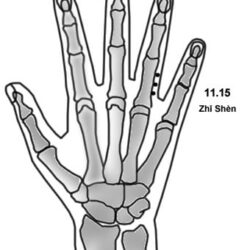

מיקום שתי נקודות, בחלק המדיאלי של האצבע המורה, על הצד הפלמרי של קו ה- D, הנקודות צמודות למפרק המטא פלנגיאלי. Dr Li Guo Zheng: יש שלוש נקודות באזור הזה. שם הנקודה Mù 木 – עץ. דיקור 0.3 – 0.2 צון קרוב לעצם. במחלות עור של הידיים דוקרים את הנקודה בצד של המחלה, למחלות האחרות דוקרים […]